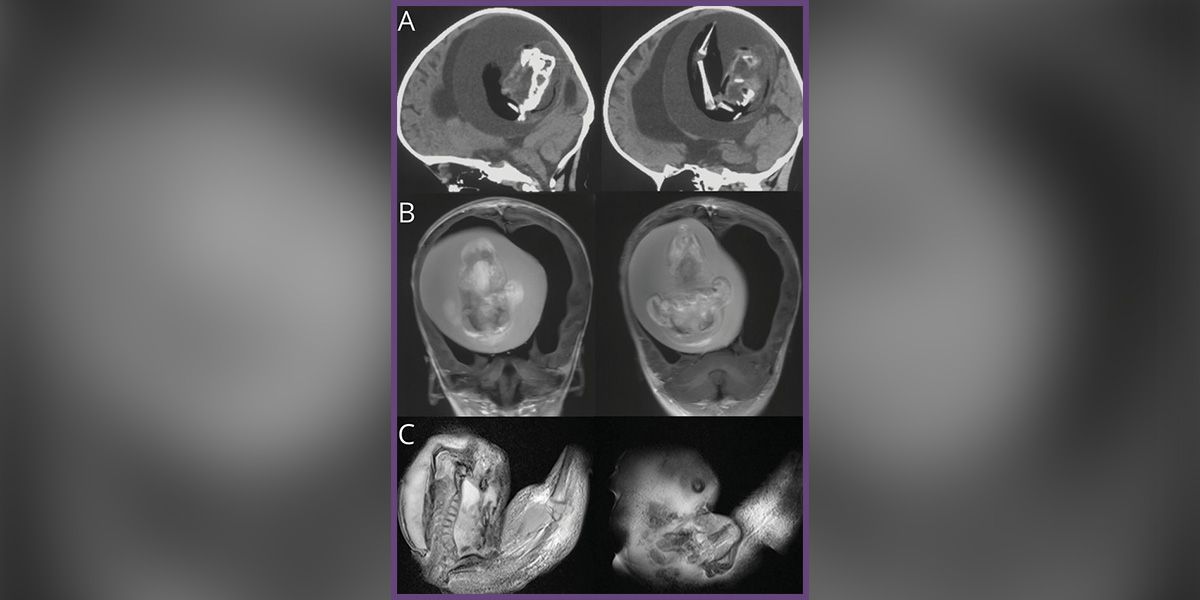

Das äußerst seltene Phänomen des "Fetus in Fetu": Der Zustand wird durch die unvollständige Trennung von eineiigen Zwillingen verursacht, die durch die Teilung einer Eizelle entstehen. Danach entwickelt sich ein Zwilling im Körper des anderen weiter. In diesem Fall im Gehirn. (Bild).